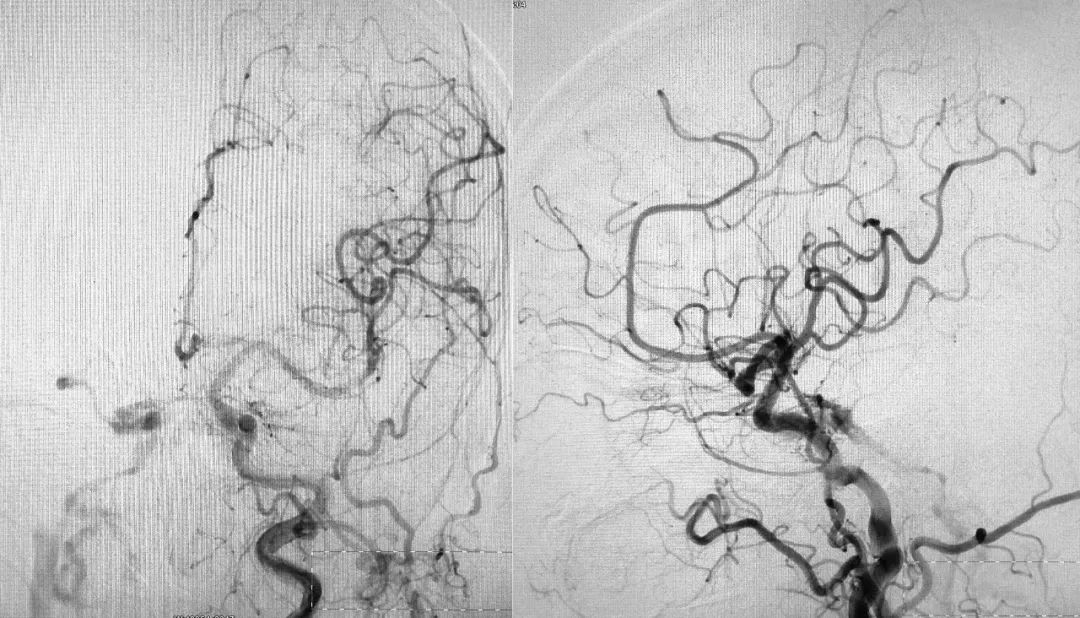

右侧颈内动脉正、侧位造影:

右侧颈内动脉造影三维重建示右侧岩下窦在汇入颈内静脉处有狭窄:

左侧颈总动脉正、侧位造影: